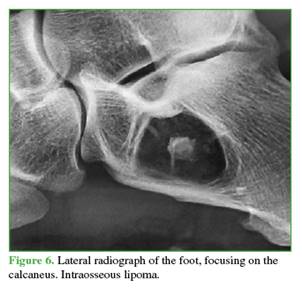

The differential diagnoses of a benign polylobulated calcaneal tumor included a simple bone cyst (Figure 4), an ABC (Figure 5), or an intraosseous lipoma (Figure 6).